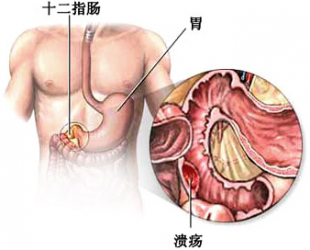

十二指肠溃疡有哪些症状,什么病因引起的

导语 十二指肠溃疡是消化科常见病之一,十二指肠任何部位都可发生溃疡,但

如何治疗十二指肠溃疡

导读 十二指肠溃疡是消化科常见病之一,十二指肠任何部位都可发生溃疡,但

十二直肠溃疡的症状

导读 十二指肠溃疡是消化科常见病之一,十二指肠任何部位都可发生溃疡,但 查看更多